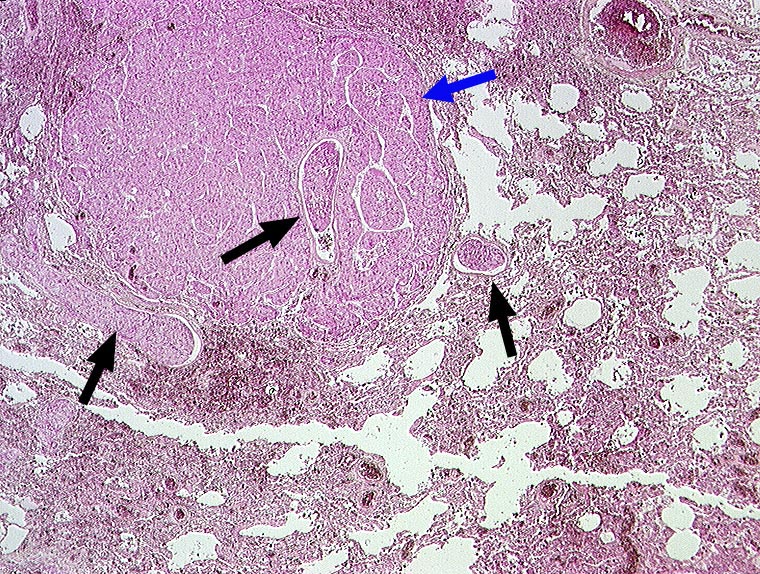

Hepatozelluläres Karzinom : Tumorembolien

Solide Tumorzellaggregate in Pulmonalarterienästen. Die Tumoremboli liegen unmittelbar im Bereich einer Metastase, welche wahrscheinlich aus einem Embolus hervorgegangen ist.

Hepatozelluläre Karzinome haben die Tendenz sich in Form von Tumorembolien in die Lungen auszubreiten.